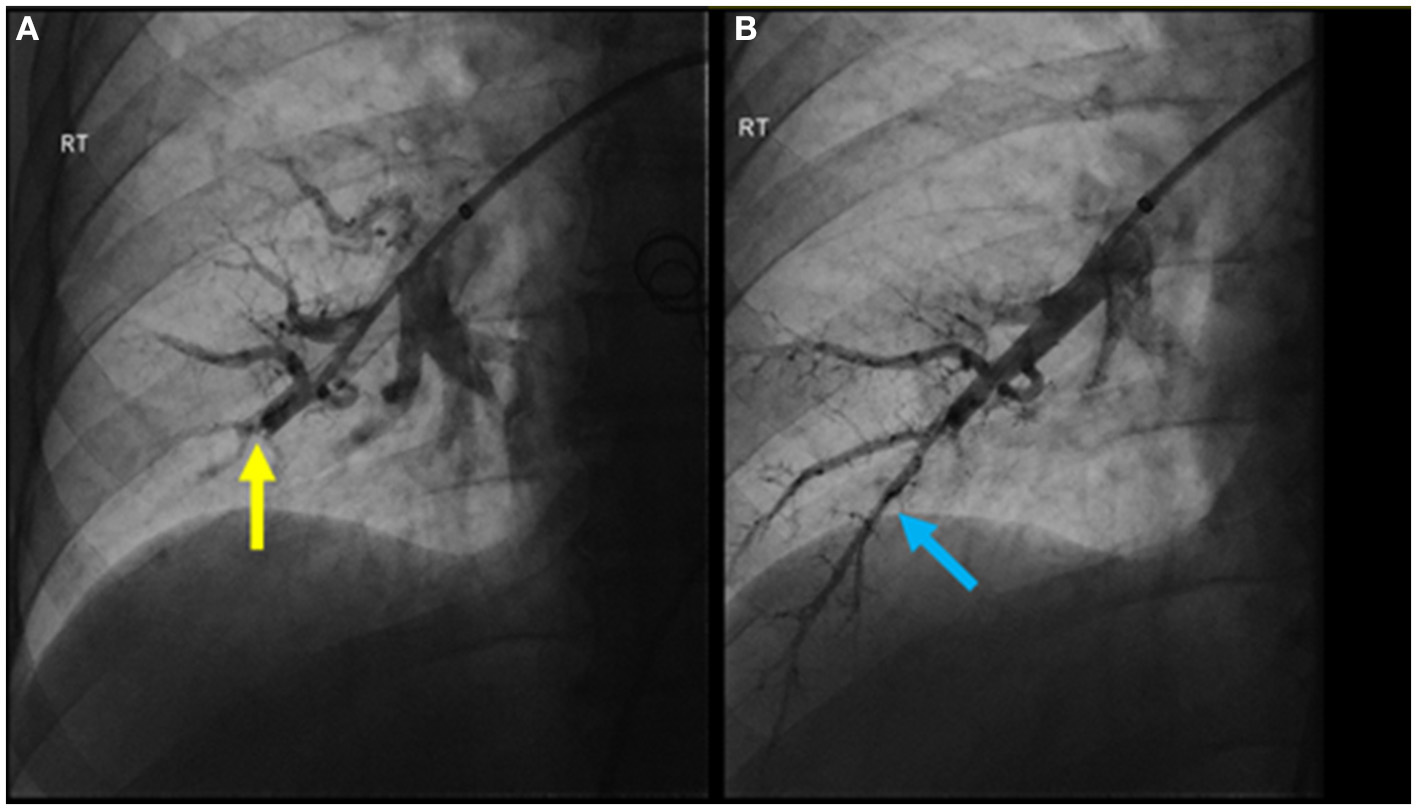

Figure 4

(A) Pulmonary angiogram pre-BPA of the anterior basal right lower lobe segmental pulmonary artery demonstrating significant impairment in flow due to a subtle web lesion (yellow arrow); (B) post-BPA pulmonary angiogram showing significant improvement in flow (blue arrow).

The patient was treated medically with apixaban, riociguat, and macitentan. After multidisciplinary discussion, the chest wall vascular malformation was hypothesized to be the most likely source of the chronic pulmonary emboli. Thus, around 1 month after the diagnosis was confirmed, the communication of the chest wall vascular malformation with the systemic veins was interrupted using interventional radiology directed embolization and surgical ligation. Four months later, the patient underwent sequential BPA sessions to treat their pulmonary thromboembolic lesions. In the initial session, access was achieved through the right common femoral vein. A 6-French vascular sheath was advanced followed by a pigtail catheter and a hydrophilic wire to gain access to the right pulmonary artery. A 0.014 in × 185 cm PT2 microwire was used to selectively access the right lower lobe anterior basal segmental branch, with significant impairment in flow due to a subtle web lesion (Figure 4A). Two balloons, measuring 2 and 3 mm, were inflated to dilate the artery and disrupt the web. Significant improvement in flow was observed post-BPA (Figure 4B).